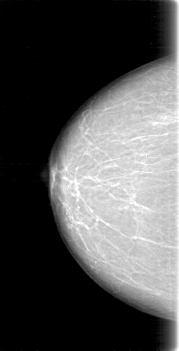

D_4091_1.RIGHT_CC

RIGHT_CC LINES 5251 PIXELS_PER_LINE 2671 BITS_PER_PIXEL 12 RESOLUTION 43.5 NON_OVERLAY